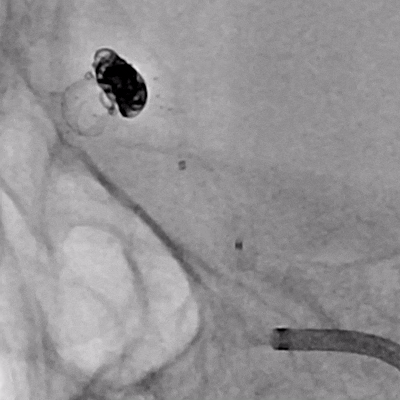

NUMEN Case 16

NUMEN Case 18